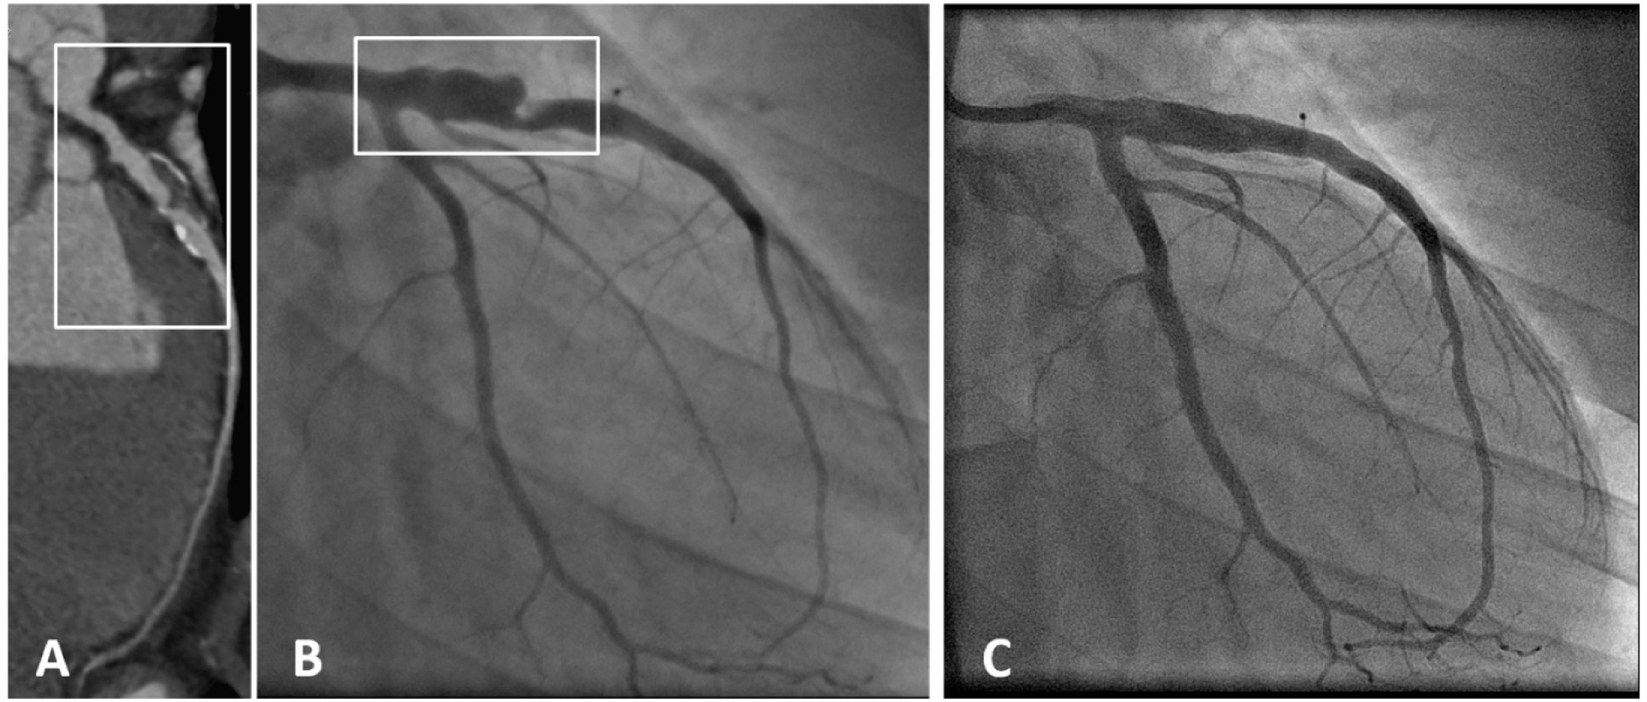

Figure 3

A patient with coronary aneurysm due to Kawasaki disease. (A) Computed tomography angiography showed a large aneurysm (maximum diameter 9 mm, extending for more than 35 mm) of the proximal left anterior descending (LAD) artery with calcific degeneration, large filling defect with thrombus and severe lumen narrowing. (B) Coronary angiography confirmed a 70% stenosis of the LAD artery with an aneurysm immediately distal to the ostium (maximum diameter 9.2 mm × 7.8 mm). (C) Final angiography demonstrating exclusion of the aneurysm using a covered stent [with permission from the report by Di Mario et al. (133)].